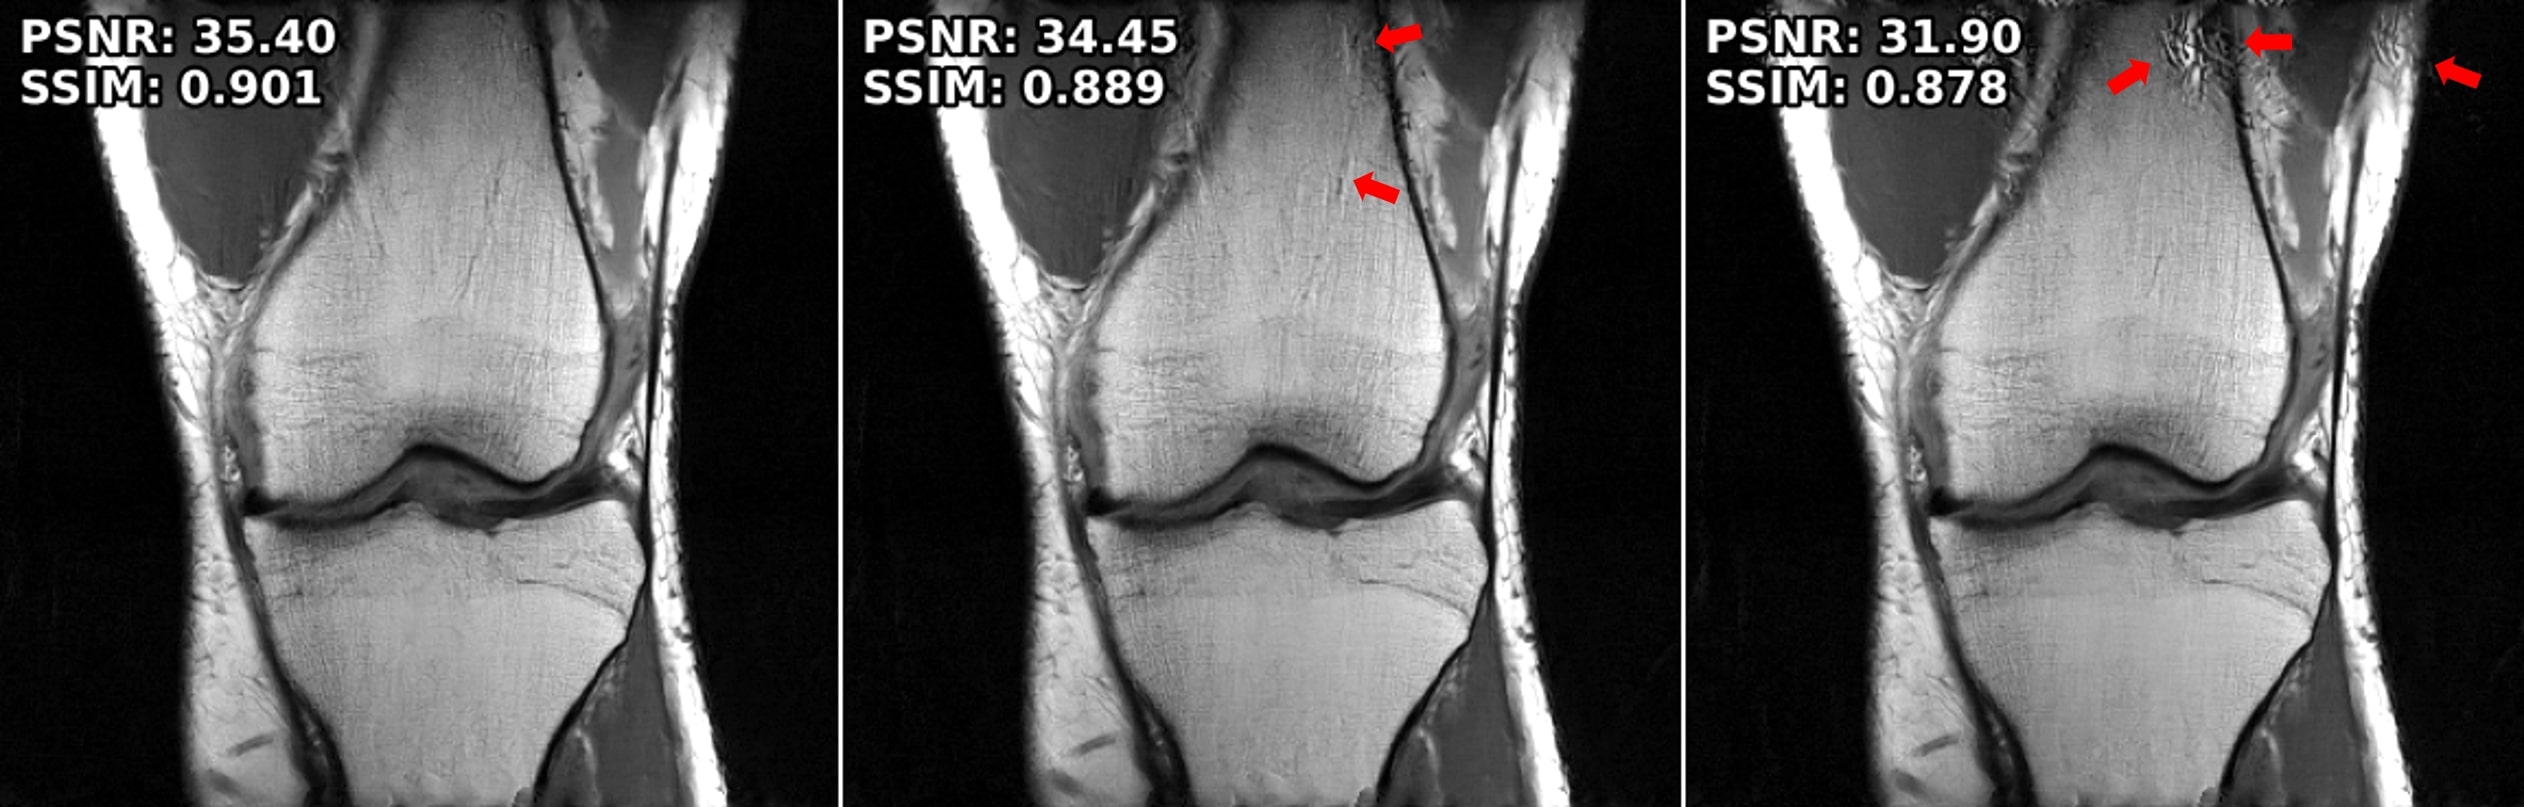

Figure 2: Representative reconstruction results for Cor-PD knee, and Ax-FLAIR brain MRI Datasets at R=4R=4. The attack inputs lead to severe disruption in the baseline MoDL reconstruction. Adversarial training improves these, albeit suffering from blurriness. SMUG fails to eliminate the attack. The proposed strategy reduces the artifacts and maintains sharpness. Furthermore it can be combined with the other strategies for further gains (last two columns).

4.2 Attack Mitigation Results

Performance Across Datasets. We first study our approach and the comparison methods on knee and brain MRI datasets at RR = 4. Fig. 2 shows that baseline PD-DL (MoDL) has substantial artifacts under attack. SMUG improves these but still suffers from noticeable artifacts. AT resolves the artifacts, albeit with blurring. Our proposed approach successfully mitigates the attacks

without any retraining, while maintaining sharpness. We note our method can also be combined with SMUG and AT to further improve performance. Fig. 4 summarizes the quantitative metrics for all test slices, consistent with visual observations.

Performance Across Attack Strengths and Blind Mitigation. We next test the methods across different attack strengths, ϵ\epsilon\in{0.01,0.02}\{0.01,0.02\}. Fig. 3 shows the results for both attack strengths using the robust training methods trained with ϵ\epsilon = 0.01 and proposed mitigation. As in Fig. 2, SMUG has artifacts at ϵ\epsilon = 0.01, which gets worse at ϵ\epsilon = 0.02. Similarly, AT struggles at ϵ\epsilon = 0.02, since it was trained at ϵ\epsilon = 0.01, leading to visible artifacts (arrows). On the other hand, our training-free mitigation is successful at both ϵ\epsilon.